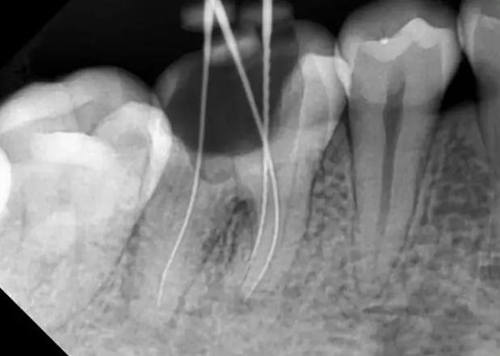

牙根內外吸收的原因不同,治療方法和預后也不一樣。因此,應根據X線和臨床表現(xiàn),區(qū)別內外吸收,選擇適應的治療方法,用X線根尖片和咬合片的表現(xiàn)區(qū)分牙根內外吸收;內吸收邊界清楚光滑,形狀多對稱,吸收部位根管粗大;外吸收邊界粗糙,密度不一,呈蠶食壯,形狀多不對稱,在破壞未穿通根管前,仍能尋找到根管的原始輪廓。偏移投照時,內吸收與根管的位置關系不變,而外吸收部位發(fā)生變化。

內吸收是從髓腔或根管內壁開始,與牙髓炎癥和細菌感染有關。一般無癥狀,多為X線照相時發(fā)現(xiàn)。應盡早行根管治療,去除感染組織后,預后良好,否則進一步發(fā)展會造成根管壁的穿孔。徹底去除內吸收部位的感染組織較為困難,充分沖洗或超聲蕩洗是有效的清潔方法,并在根管內封Ca(OH)2蝴劑1周后再根充。由于內吸收過大,根管壁很薄,應避免過大壓力,要選用Ca(OH)2基質的蝴劑與牙膠根充,根管壁穿孔較小,可用 Ca(OH)2糊劑根充3個月,誘導硬組織形成后再根充;或用根管水泥(MTA)根管內根充并修補。較大的根管壁穿孔可用MTA從根管內或手術修補。內吸收近根尖區(qū)可考慮根尖手術,多根牙可考慮截根術。

牙根外吸收是從牙周組織開始,原因多為創(chuàng)傷,矯正力過大,埋伏牙,牙齒漂白,再植牙和根尖周炎癥等。因根尖周炎造成的根尖區(qū)外吸收處理方法同內吸收,其他因素造成的外吸收采用相應的對因處理和根管治療。